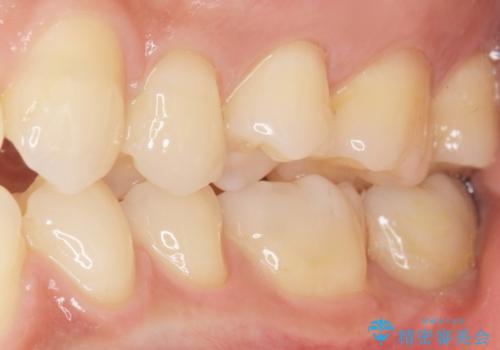

気にされていたフロスをした時のにおいがなくなり、喜んで頂けました。

治療終了後半年のメンテナンス時には「咬み合わせもばっちりです!」とおっしゃって下さいました。

インレーの種類:セラミックインレー e-max press